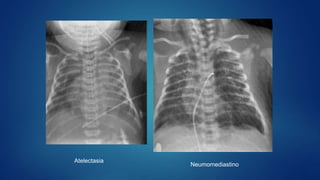

Atelectasia

Neumomediastino